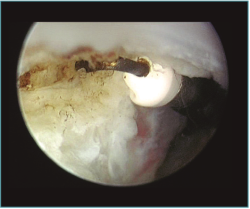

Figura 10. Caso 6. Visión artroscópica desde el portal anteromedial del engrosamiento y la hipervascularización de la cápsula anterior del codo, responsable del déficit de extensión.

Figura 11. Caso 6. Visión artroscópica desde el portal anteromedial de la extracción del fragmento osteocondral inestable de la cabeza del radio.

Figura 12. Caso 6. Visión artroscópica desde el portal anteromedial tras la resección del fragmento inestable. Se aprecia el engrosamiento y enrojecimiento de la cápsula anterior.